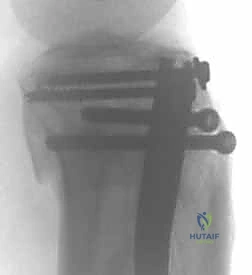

4. إدخال المسمار النخاعي والتثبيت النهائي

يتم تمرير مسمار التيتانيوم بدقة داخل العظم. وبمجرد التأكد من موضعه المثالي بالأشعة، يقوم البروفيسور هطيف بإدخال المسامير التشابكية (Locking Screws) العرضية في أعلى وأسفل المسمار لضمان التثبيت المطلق.

- التثبيت التشابكي (Interlocking): يتم تمرير مسامير صغيرة عرضية عبر العظم والمسمار النخاعي في الطرفين العلوي والسفلي، مما يمنع دوران العظم حول المسمار ويحافظ على طول الساق الطبيعي بدقة متناهية.